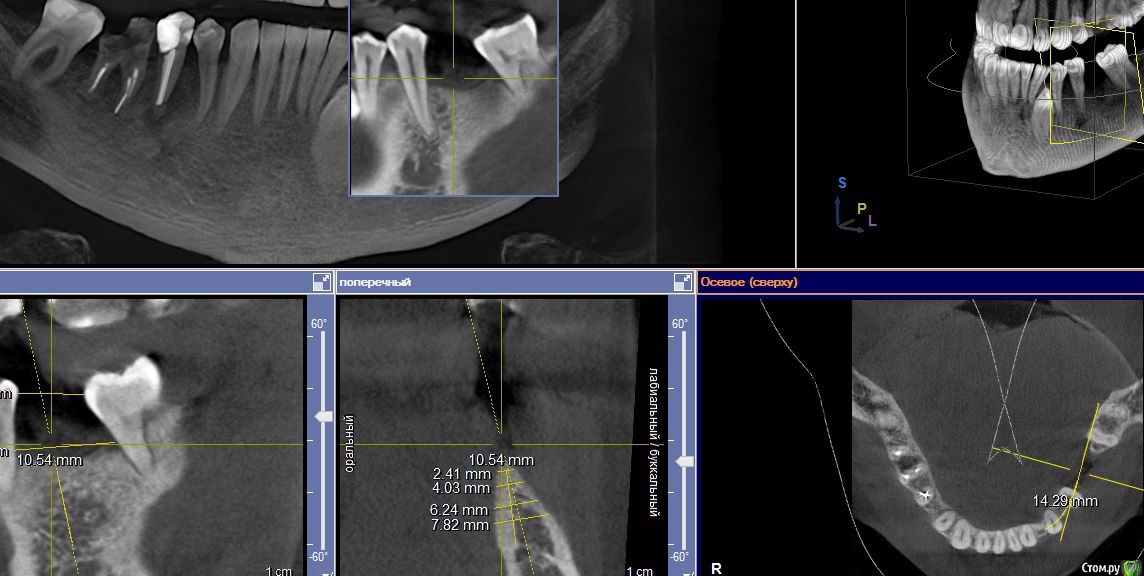

Paco Rabanne Опубликовано 27 октября, 2015 Поделиться Опубликовано 27 октября, 2015 Помогите пожалуйста в планировании.Пациент крупный мужчина, спортсмен, ест много.Зона 36зуба. Медио-дист расстояние по кости около 14мм, в полости рта 11мм. Медиальный наклон 37з. Ортодонтия исключена. Тонкий биотип тканей. Предварительно проведено увеличение зоны прикрепленной десны.Вопросы:1.Сколько ставите имплантов в подобной ситуации? Для одного импланта много места, для двух будет мешать 37 (его фрезой будешь задевать наверное).2. Как лучше аугментировать? Одномоментно с имплантацией, или лучше сначало аугментация (ваш вариант метода) , а потом имплантация?Фото на момент снятия швов после СДТ. Спасибо всем кто отзовется. Понимаю, что сколько людей столько и мнений, интересстны все. Ссылка на комментарий

red_butler Опубликовано 27 октября, 2015 Поделиться Опубликовано 27 октября, 2015 1.Сколько ставите имплантов в подобной ситуации? один Мне кажется срезы Кт выставлены не корректно. Ссылка на комментарий

Paco Rabanne Опубликовано 27 октября, 2015 Автор Поделиться Опубликовано 27 октября, 2015 (изменено) один Мне кажется срезы Кт выставлены не корректно. Спасибо.Что Вы имеете ввиду "не корректно"? В медио-дист направлении ровно по середине между 35 и 37з. Изменено 27 октября, 2015 пользователем Paco Rabanne Ссылка на комментарий

red_butler Опубликовано 27 октября, 2015 Поделиться Опубликовано 27 октября, 2015 А как по вашему надо?http://s017.radikal.ru/i429/1510/c6/77848b8dff72.jpg 2 Ссылка на комментарий

Paco Rabanne Опубликовано 27 октября, 2015 Автор Поделиться Опубликовано 27 октября, 2015 (изменено) http://s017.radikal.ru/i429/1510/c6/77848b8dff72.jpgДа, я согласен. В этой программе (Сирона) этот срез у меня не получается выставлять так, я понял, что он выставляется автоматически, а я могу только в двух других плоскостях менять направление осей. Если я не прав, подскажите пожалуйста как это сделать? Изменено 27 октября, 2015 пользователем Paco Rabanne Ссылка на комментарий

Доктор Добрых Дел Опубликовано 27 октября, 2015 Поделиться Опубликовано 27 октября, 2015 (изменено) Да, я согласен. В этой программе (Сирона) этот срез у меня не получается выставлять так, я понял, что он выставляется автоматически, а я могу только в двух других плоскостях менять направление осей. Если я не прав, подскажите пожалуйста как это сделать? Да, я согласен. В этой программе (Сирона) этот срез у меня не получается выставлять так, я понял, что он выставляется автоматически, а я могу только в двух других плоскостях менять направление осей. Если я не прав, подскажите пожалуйста как это сделать? Справа где выбор инструментов нажимаете на значок изображающий нижнюю челюсть и в открывшимся окне выбираете форму дуги. Изменено 27 октября, 2015 пользователем Доктор Добрых Дел Ссылка на комментарий

Paco Rabanne Опубликовано 27 октября, 2015 Автор Поделиться Опубликовано 27 октября, 2015 Справа где выбор инструментов нажимаете на значок изображающий нижнюю челюсть и в открывшимся окне выбираете форму дуги.Спасибо, поигрался с формой и размером дуги, стало лучше. Ссылка на комментарий